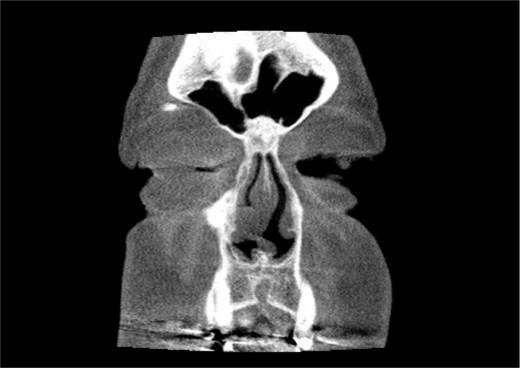

A 67-year-old male presented to our outpatient office with complaints of increasing bouts of right sided nasal bleeding for the preceding twelve months. He had been able to control the epistaxis with pressure and oxymetazoline nasal spray; however, a recent Emergency Room visit for persistent nasal bleeding prompted a referral to our office. The patient denied nasal trauma or other sinonasal problems in the past or present. He was not taking any anticoagulant or antiplatelet therapies. Nasal endoscopy revealed a soft, pale, non tender mass on the caudal end of the right inferior turbinate. Coagulated blood was noted over the anterior portion of this mass, without any vascular prominence or bleeding appreciated over the septal wall. This indicated the nasal mass was the site of recurrent epistaxis. Non-contrast computed tomography (CT) of the sinuses (Figs 1 and 2), showed a soft tissue prominence at the same area seen on endoscopy (Fig. 3).

Coronal non-contrast CT scan images of soft tissue lesion on right inferior turbinate.